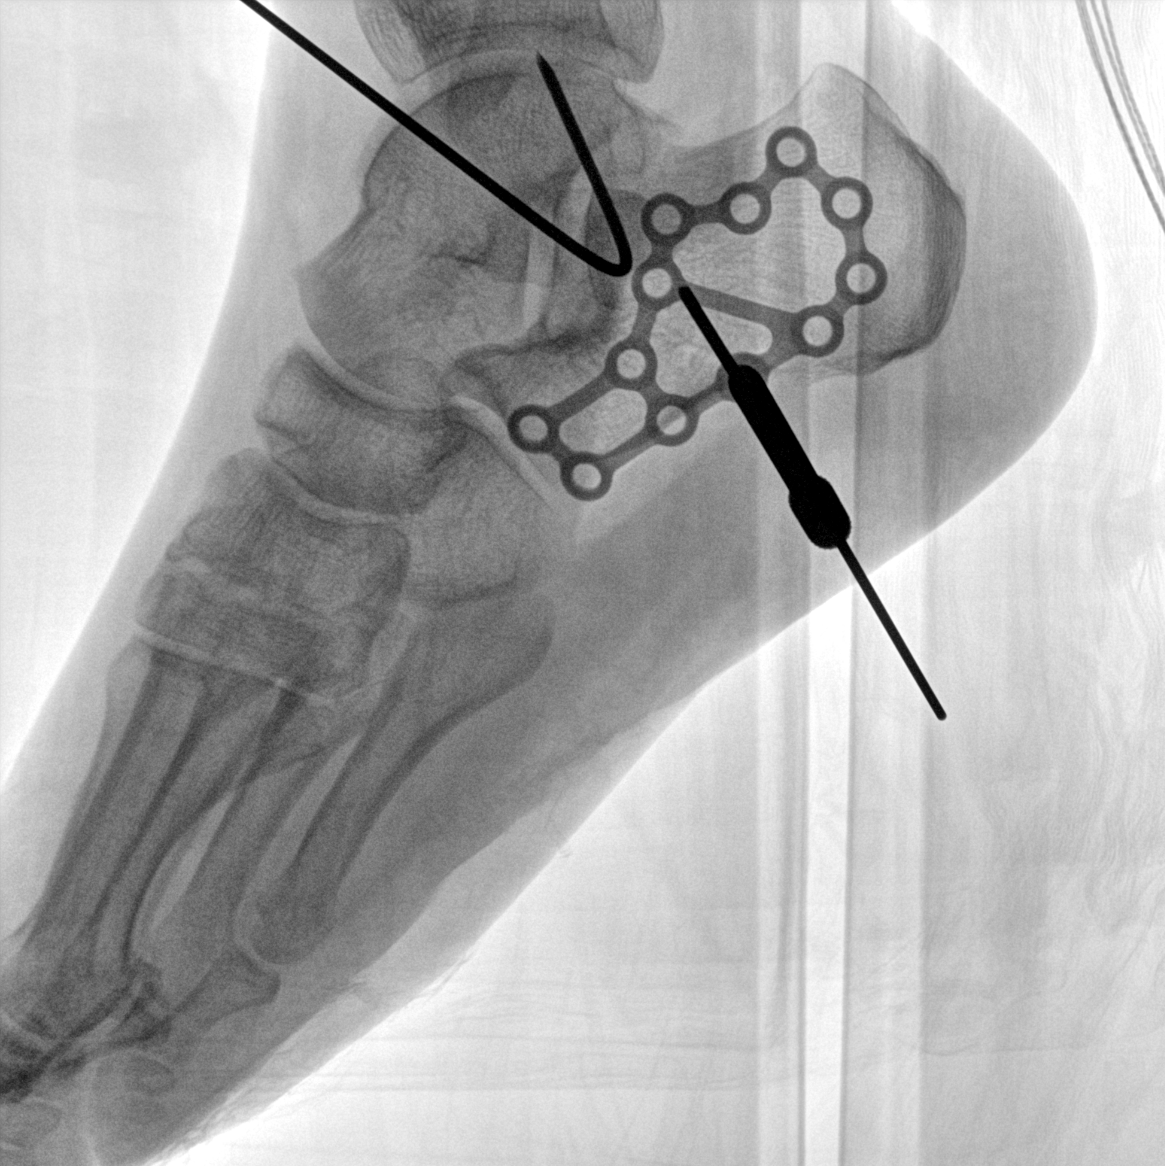

術(shù)中三維成像和橫斷面圖像提供多角度的手術(shù)診斷信息,輔助醫(yī)生進(jìn)行術(shù)中評估判斷,諸如骨折復(fù)位情況和內(nèi)植入螺釘?shù)某叽绾臀恢?,輔助手術(shù)更好地完成。